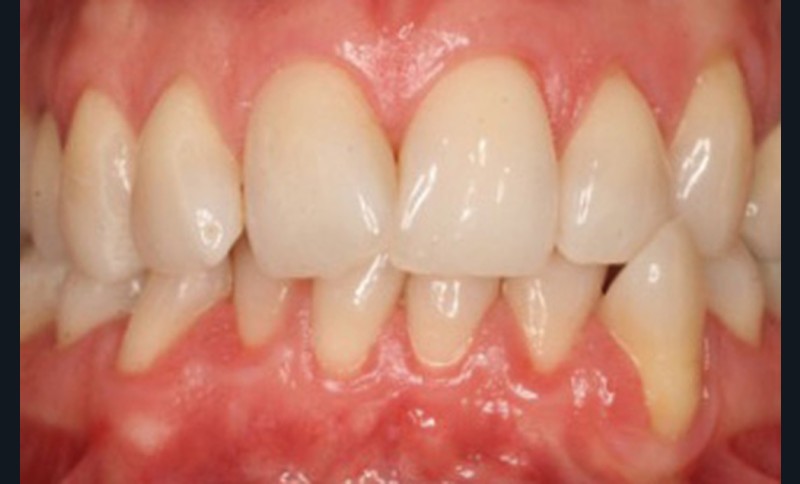

Le Pr Olivier Sorel insistera sur l’importance du respect des formes et des proportions anatomiques, pour éviter de voir apparaître, notamment chez les adultes, de très inesthétiques triangles noirs lors de la phase d’alignement (fig. 6a-b). Il présentera sa démarche diagnostique (évaluation de la forme des dents et de la dysharmonie dento-dentaire, fig. 7a-c) et l’intégration de la réduction amélaire proximale au plan de traitement, afin de s’assurer, en fin de traitement, la présence de papilles gingivales et donc d’un sourire harmonieux (fig. 8a-d).

Les Drs Marie Clément et Clara Marcoux aborderont ensuite les différents apports de la dentisterie esthétique aux traitements orthodontiques. Les problèmes de dyschromies isolées ou généralisées, congénitales ou acquises seront développés ainsi que les anomalies de proportions dentaires (dents riziformes…), le maquillage (transformation d’une canine en incisive latérale…) et le remplacement des dents antérieures. Les auteurs présenteront l’intérêt du Digital Smile Design dans le diagnostic et la communication et l’arsenal thérapeutique à notre disposition pour améliorer la satisfaction de nos patients (éclaircissement, traitement des taches de l’émail, composites stratifiés, fig. 9a-d).